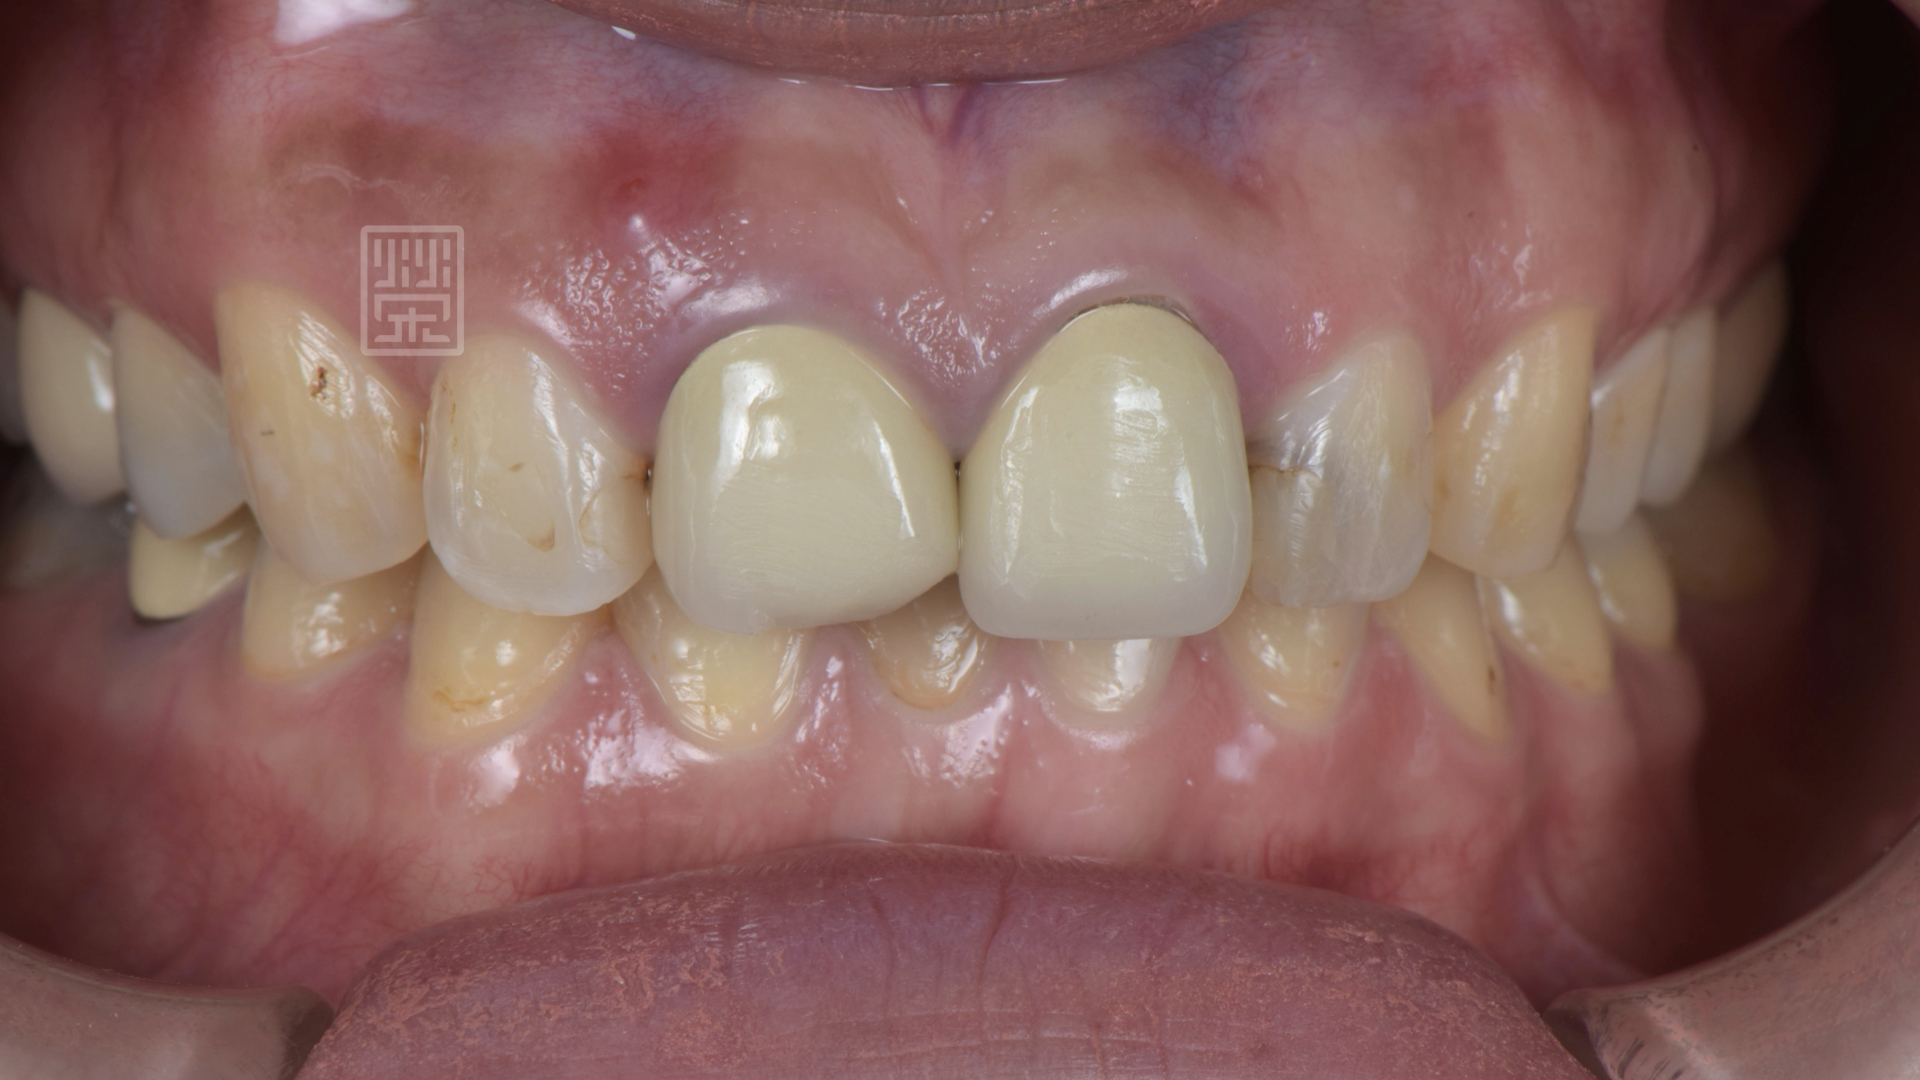

榮醫師檢查後,發現右側門牙根尖有瘻管,右側門牙需要根管治療,預計更換兩個全瓷冠,其餘利用貼片恢復美觀。

但是,就是這個但是......將牙冠、鑄釘移除後,發現右側中門牙牙齒有裂痕,所以就需要改變治療計畫,將右側中門牙改成植牙,解釋後鄧小姐理解這個狀況,安排拔牙與植牙療程。

假牙拆除後,發現右邊中門牙有裂痕